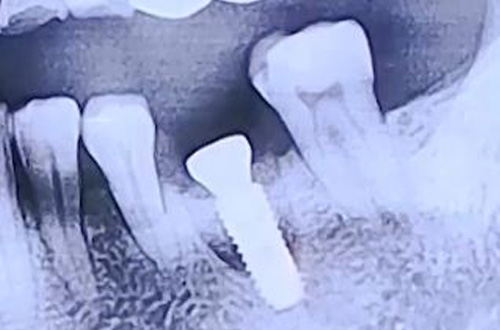

BEFORE

치료 유형 어금니 즉시 임플란트

어금니의 심한 통증으로 내원해 주신 환자분이십니다.

엑스레이 상으로는 주변 잇몸이 약해진 것 외에 큰 문제가 발견되지 않아

CT를 찍어보니 치아가 세로로 크게 파절되어 이로 인한 잇몸 염증이 있으셨는데요.

뿌리 부분이 파절되었으므로 발치 후 즉시 임플란트를 결정하였고,

발치한 자리에 임플란트를 식립하고 빈 공간을 뼈이식으로 채워드렸고,